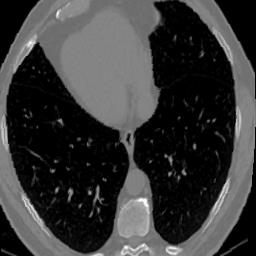

In clinical practice, well-aligned multi-modal images, such as Magnetic Resonance (MR) and Computed Tomography (CT), together can provide complementary information for image-guided therapies. Multi-modal image registration is essential for the accurate alignment of these multi-modal images. However, it remains a very challenging task due to complicated and unknown spatial correspondence between different modalities. In this paper, we propose a novel translation-based unsupervised deformable image registration approach to convert the multi-modal registration problem to a mono-modal one. Specifically, our approach incorporates a discriminator-free translation network to facilitate the training of the registration network and a patchwise contrastive loss to encourage the translation network to preserve object shapes. Furthermore, we propose to replace an adversarial loss, that is widely used in previous multi-modal image registration methods, with a pixel loss in order to integrate the output of translation into the target modality. This leads to an unsupervised method requiring no ground-truth deformation or pairs of aligned images for training. We evaluate four variants of our approach on the public Learn2Reg 2021 datasets \cite{hering2021learn2reg}. The experimental results demonstrate that the proposed architecture achieves state-of-the-art performance. Our code is available at https://github.com/heyblackC/DFMIR.